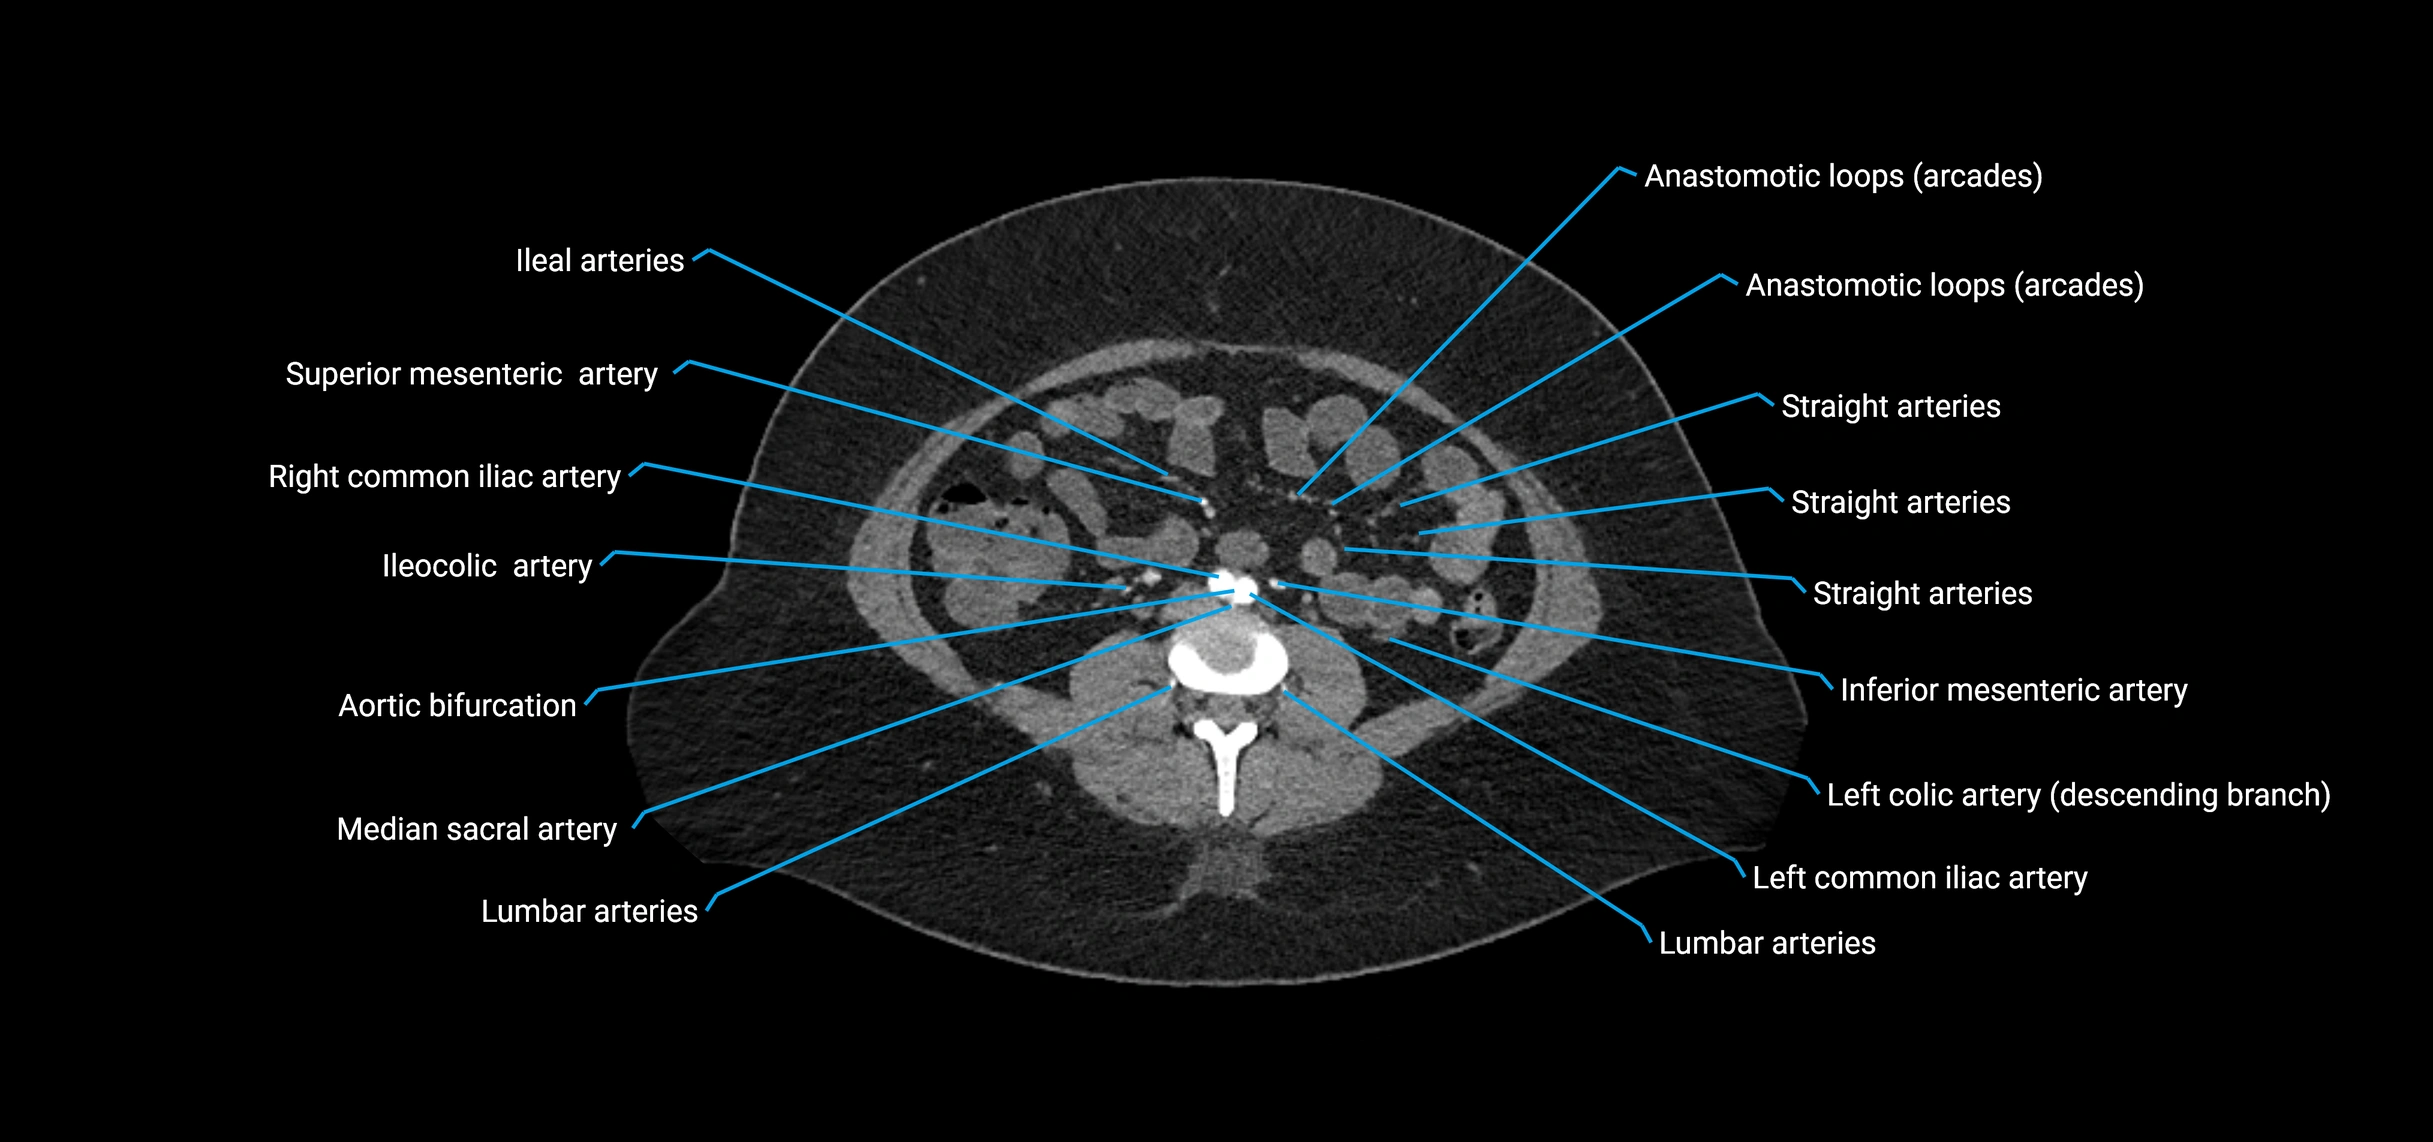

Contrast-enhanced CT (CTA):

• Gold standard for abdominal aortic imaging

• Provides excellent detail of lumen, wall, aneurysm, thrombus, and branch vessels

• Multiplanar and 3D reconstructions help in aneurysm measurement, stent graft planning, and dissection evaluation

• Detects acute rupture, traumatic injury, or occlusion with high sensitivity